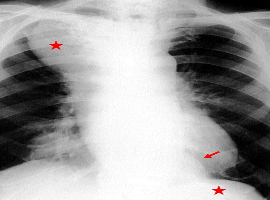

Citation: Mancini R, Pattaro G, Ioni L, et al. Huge Para-esophageal Mass of the Mediastinum Mimicking Achalasia: Case Report. Clin Image Case Rep J. 2021; 3(2): 141.